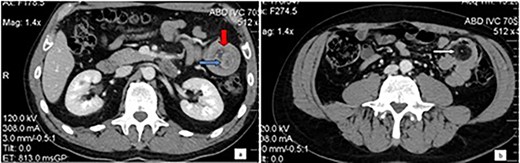

Physical examination disclosed tenderness in the left upper quadrant without rebound tenderness or muscle guarding. Biochemical and hematological investigations were unremarkable. A contrast-enhanced computed tomography of the abdomen was performed and showed the typical target sign of a small intestinal intussusception along the left upper quadrant and a well-defined, low-density tumor in the intussusception (Fig. 1).

Computed tomography of the abdomen: Bowel-within-bowel configuration in which the layers of the bowel are duplicated forming two concentric enhancing rings by the inner bowel (blue arrow) and the folded edge of the outer bowel (red arrow). Invaginated mesenteric fat and vessels are also visible (a). Even further distally within the jejunum the lead point is visualized as an intraluminal mass with fat attenuation, compatible with lipoma (arrow) (b).